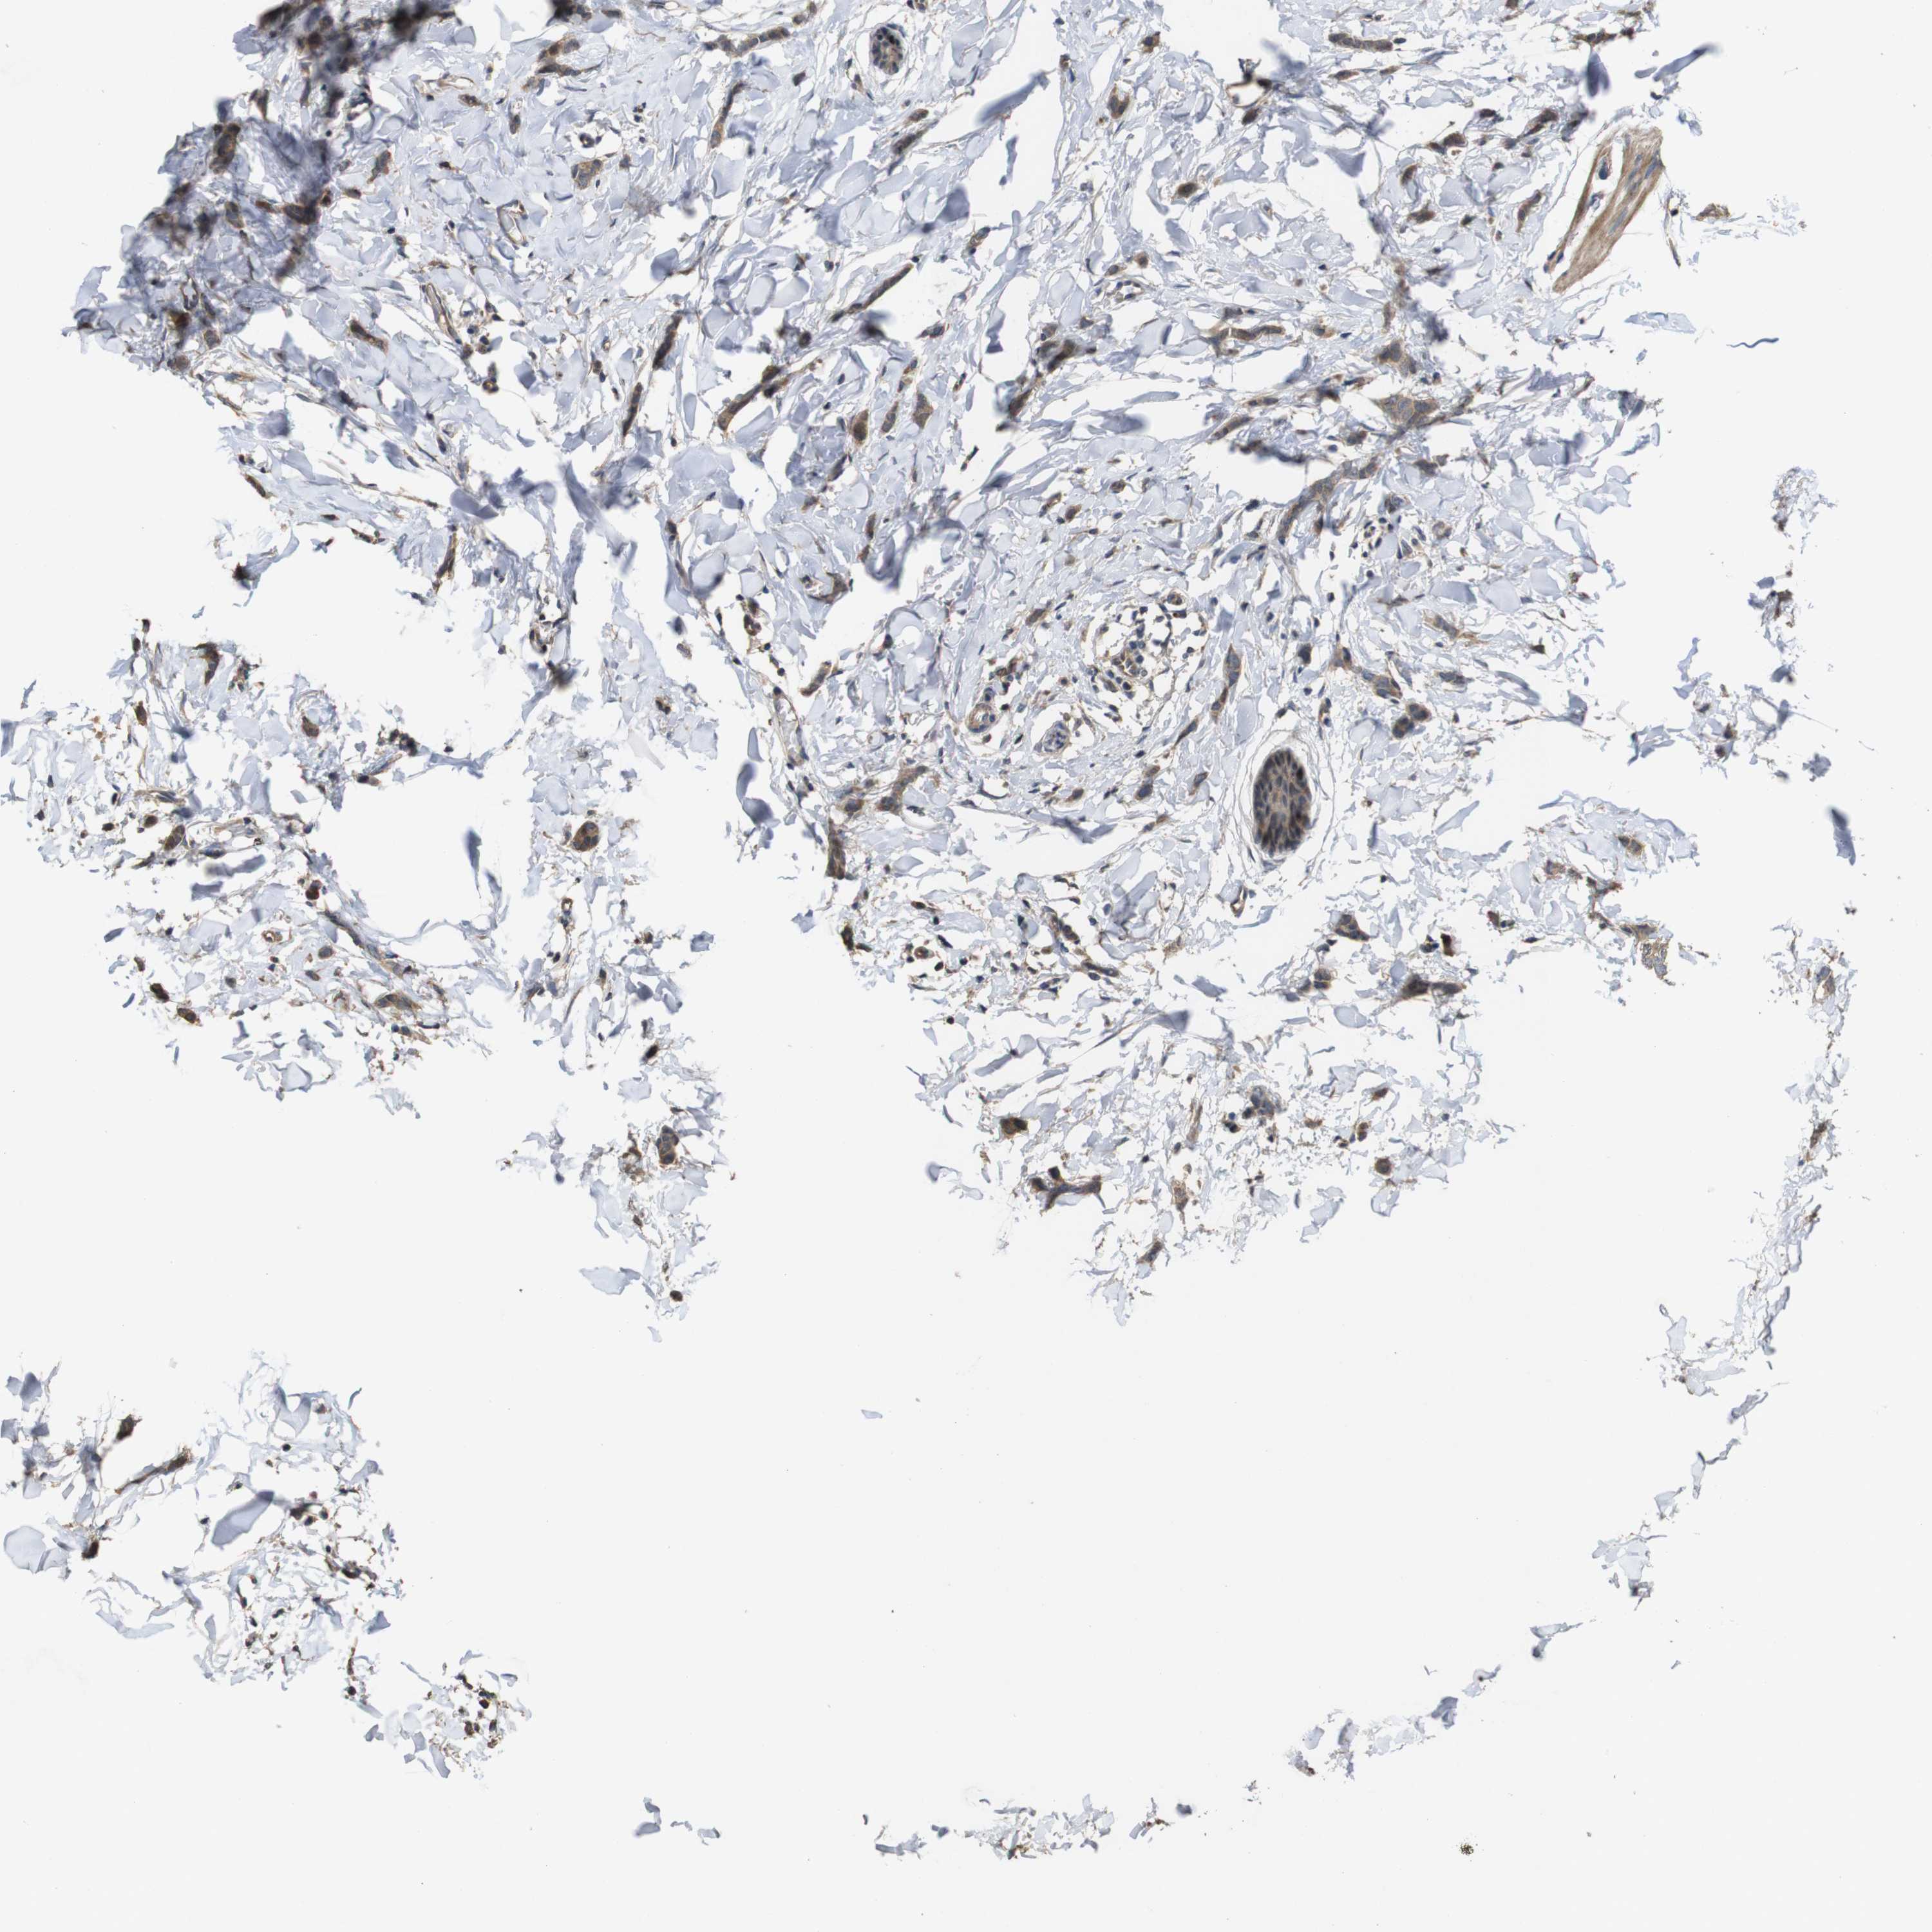

BRCA TCGA BRCA VALIDATION PROTEIN EXPRESSION

ANTIBODIES

AND

VALIDATION